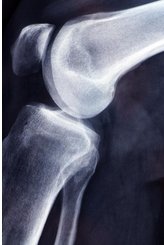

무릎 연골 손상 증상에 대해 제대로 살펴보도록 하겠습니다. 무릎 연골 손상은 무릎 관절에 있는 연골이 손상되거나 파열되는 상태를 말합니다. 연골은 뼈와 뼈 사이에 있는 연질 조직으로, 뼈의 마찰을 줄여주고 충격을 흡수하는 역할을 합니다. 무릎 연골 손상은 스포츠나 사고로 인해 발생할 수 있으며, 나이가 들면서 연골이 닳아서 생길 수도 있습니다

무릎 연골 손상은 어떻게 치료해야 할까요? 일반적으로 비수술적 치료와 수술적 치료로 나눌 수 있습니다. 비수술적 치료는 약물치료, 물리치료, 주사치료, 운동치료 등이 있습니다. 수술적 치료는 관절내시경 수술, 연골 이식술 등이 있습니다. 손상의 정도와 위치, 개인의 나이와 건강 상태, 활동 수준 등에 따라 적절한 치료방법을 선택해야 합니다.